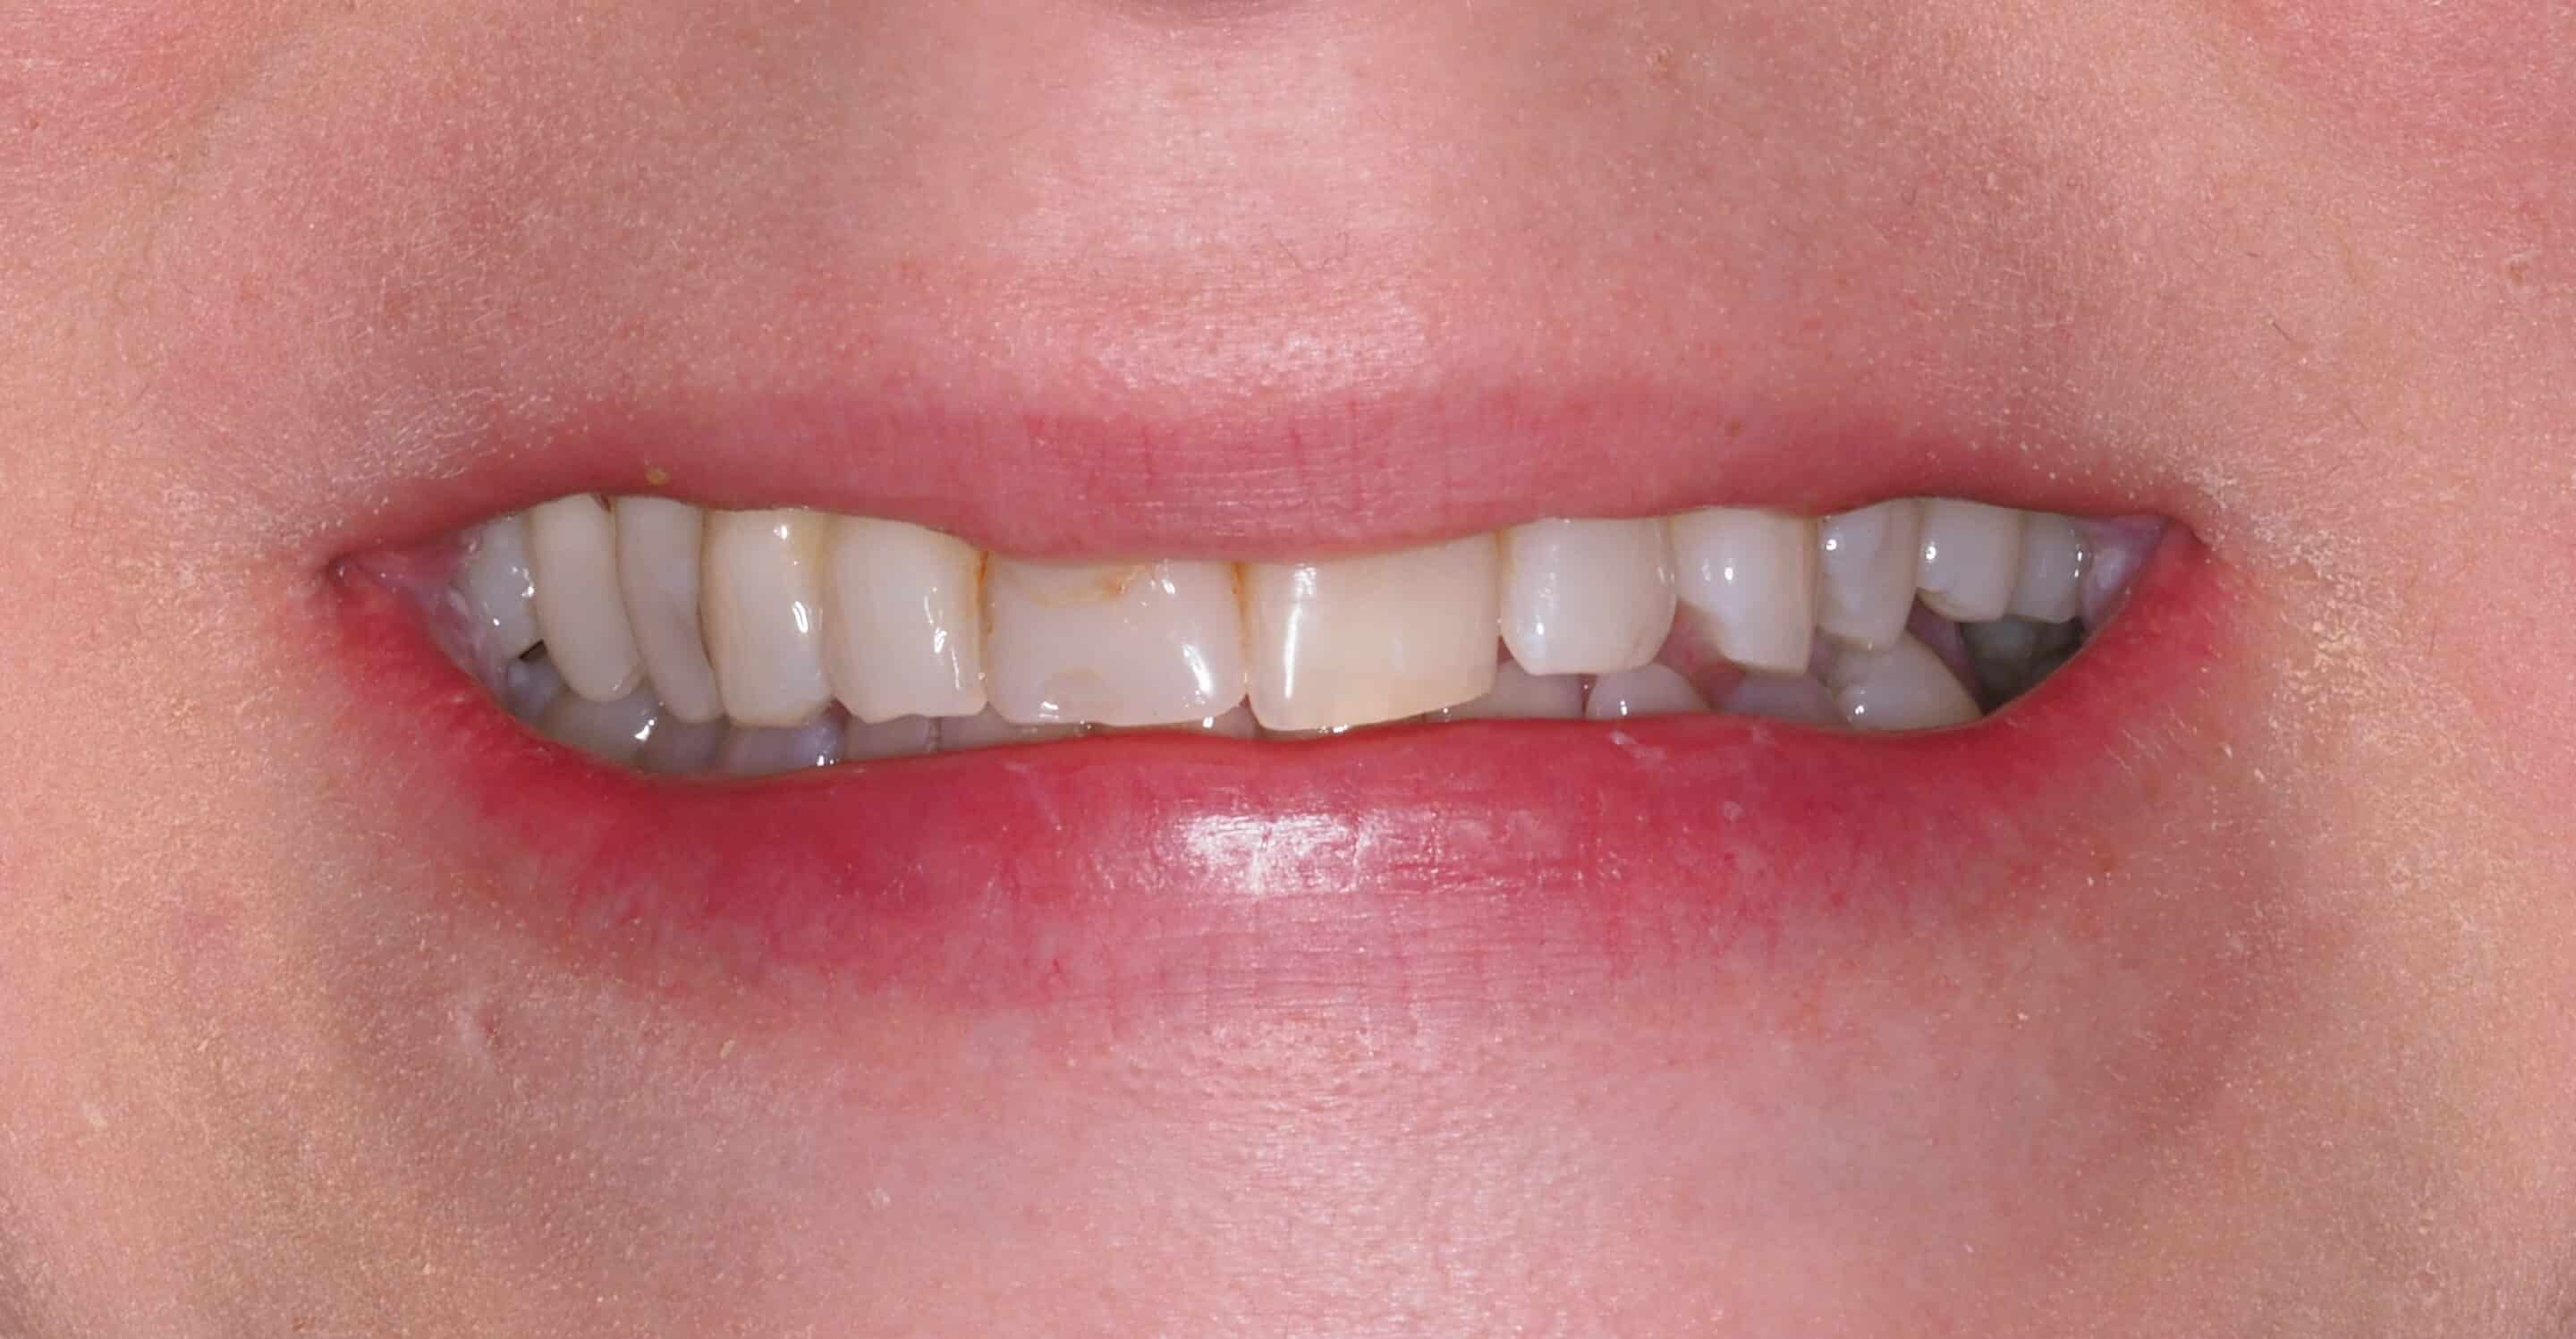

Before and After Image Gallery